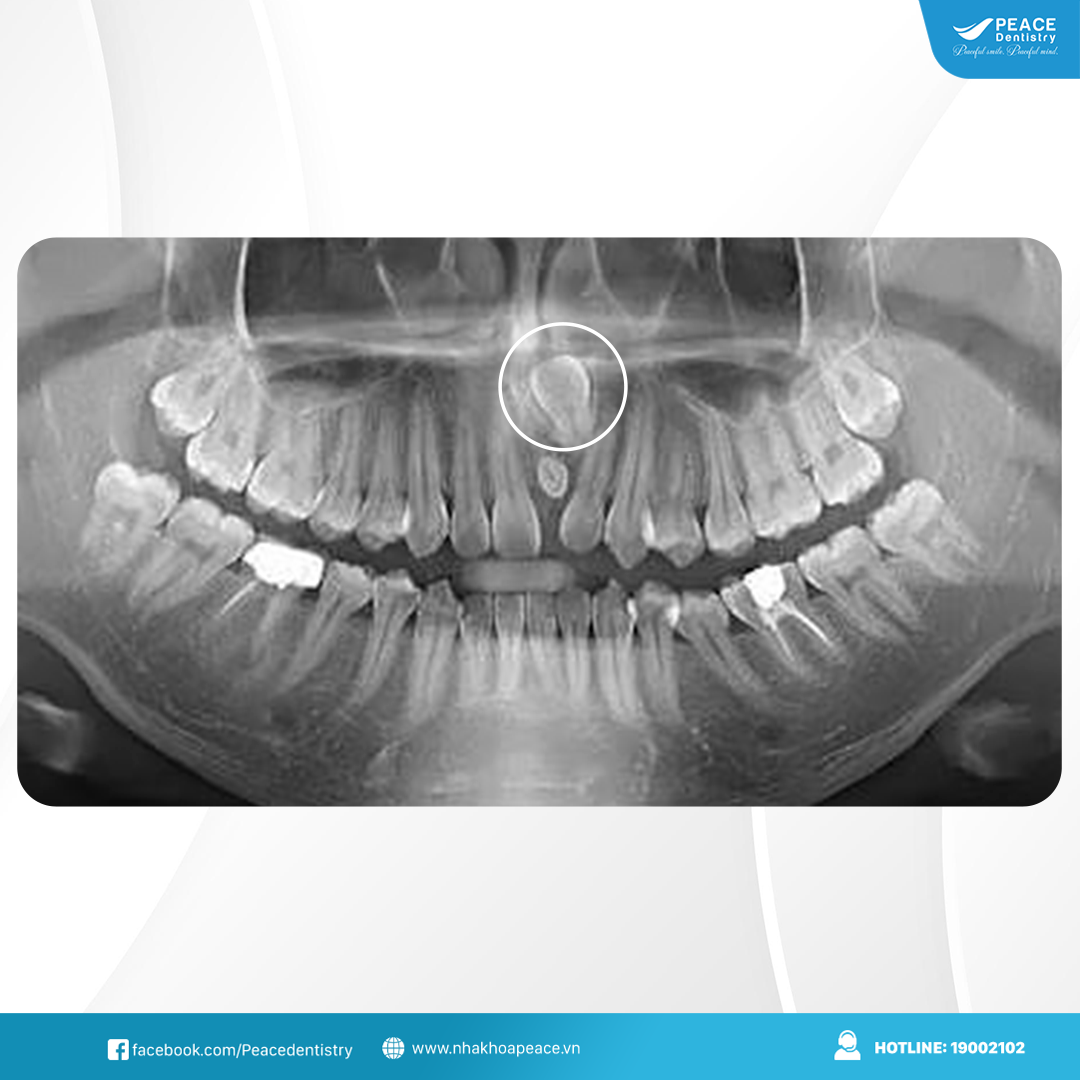

Răng mọc ngầm là tình trạng chiếc răng không thể trồi lên đúng vị trí trên cung hàm mà bị kẹt lại một phần hoặc toàn bộ trong nướu, thậm chí trong xương hàm. Phần lớn trường hợp xảy ra ở răng khôn (răng số 8), tuy nhiên răng nanh, răng cửa hoặc răng hàm nhỏ cũng có thể gặp tình trạng này.

Do nằm ẩn bên dưới, răng mọc ngầm thường khó nhận biết bằng mắt thường và chỉ được phát hiện khi có triệu chứng hoặc qua phim X-quang.

(Răng mọc ngầm là tình trạng khá phổ biến)(**)

(Răng khôn mọc ngầm là trường hợp thường gặp)(**)